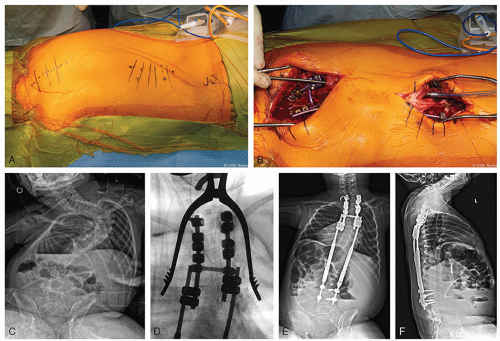

When using hooks exclusively at an anchor site, it is recommended to add a cross-link for augmentation of stability and a claw configuration (Figure 8.3)

In cases of poor bone quality or perceived diminished implant strength, short rods can be added into the proximal construct to increase local stability or even to allow for fusion with staged insertion of the growing construct at a later date (see Figures 8.3 and 8.4)

Can be either done with a single long incision or smaller incisions directly over the anchor levels and the rod connector(s) (Figure 8.4)

![]() Figure 8-4 ▪ A, Intraoperative photograph of 2-incision technique for placement of growing instrumentation with planned subfascial tunneling. B, Passage of rod in the subfascial space with the assistance of a chest tube. C, Preoperative posteroanterior (PA) radiograph of a patient with scoliosis secondary to spinal cord injury. D, Intraoperative fluoroscopic image of a double-claw hook construct over 3 segments. E, Postoperative PA radiograph after insertion of magnetically controlled growing rod (MCGR). F, Postoperative lateral radiograph after insertion of MCGR. (Courtesy of Children’s Orthopaedic Surgery Foundation.)